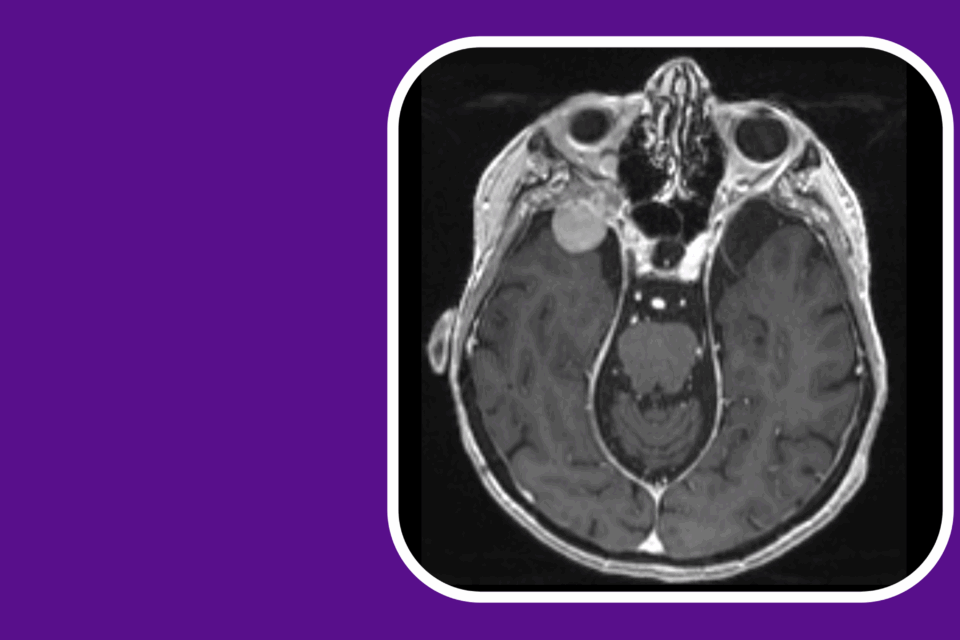

TONES for a Spheno-Orbital Meningioma in the Setting of Extensive Sinus Pneumatization

With the tumor impacting vision, transorbital neuroendoscopic surgery allowed for tumor resection and complete optic nerve decompression while minimizing risk of sinus violation.